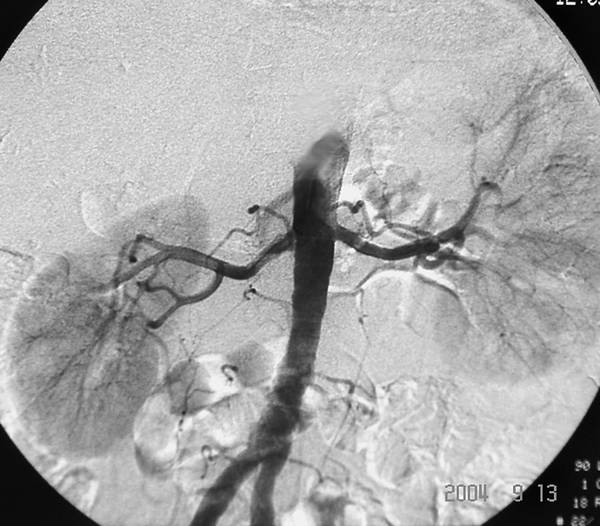

В последние годы широкое распространение получил метод цифровой субтракционной ангиографии. Он основан на цифровой обработке световых сигналов при помощи компьютера, что позволяет получить изображение только тех объектов, которые содержат контрастное вещество (рис.). При этом костные структуры и мягкие ткани не видны. По сравнению с традиционной, цифровая субтракционная ангиография обладает рядом преимуществ: малой инвазивностью, полипозиционностью и высокой информативностью.

Цифровая субтракционная ангиограмма.